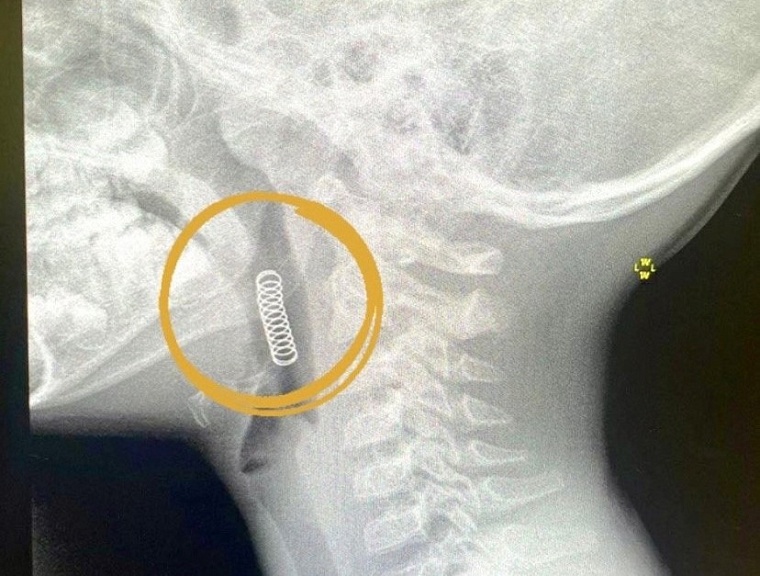

В Ишиме врачи спасли шестилетнего мальчика с застрявшей пружинкой в горле

Мальчик случайно ее проглотил, когда играл.

В Областной больнице №4 Ишима произошел нестандартный случай — к врачам привезли шестилетнего мальчика с пружиной от игрушки в глотке. Ребенок случайно проглотил ее, когда играл. Пружина застряла между надгортанником и небной миндалиной.

«Для удаления инородного тела было решено применить общую анестезию. Совместно с врачом-анестезиологом Талайбеком Асыранкуловым инородное тело было удалено. Маленький пациент после наблюдения отпущен домой», — рассказал врач-оториноларинголог Александр Плетнёв.

Фото: департамент здравоохранения Тюменской области